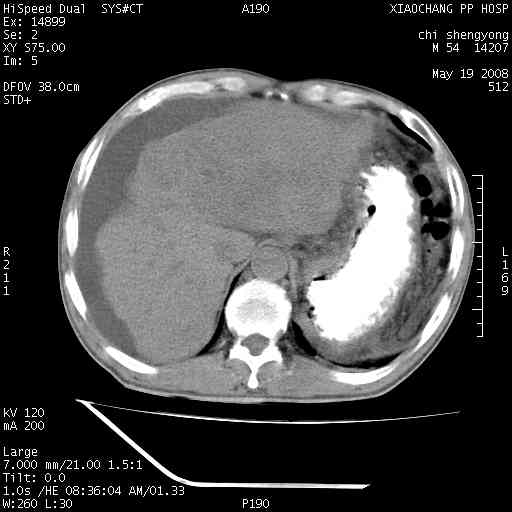

以下是引用zjzjr在2008-5-21 10:52:00的发言:[br]肝左叶巨块型肝癌伴门静脉左支瘤栓形成.肝硬化、腹水,胃底静脉曲张,脾术后改变。

以下是引用随光逐影在2008-5-21 16:20:00的发言:[br]1)肝左叶肝癌伴门静脉左支瘤栓形成,腹膜后淋巴结转移。2)肝硬化、腹水、胃底静脉曲张。3)胆囊炎。4)脾脏缺如,为切除术后所致。